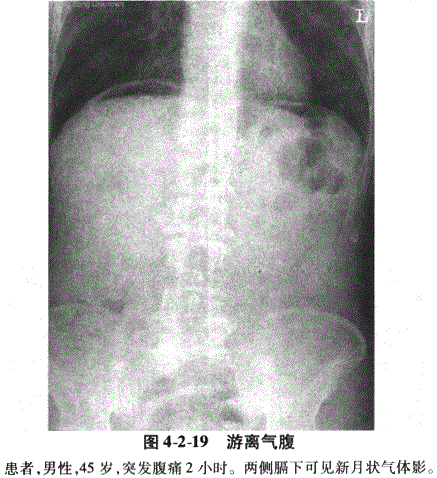

主要出现气腹、腹腔内积液、腹脂线异常和麻痹性肠胀气等表现(图4-2-19)。除游离气腹征象出现较早外,其他征象显示一般在发病后6小时以上。游离气腹的X线表现为膈下游离气体。没有游离气腹征象并不能排除消化道穿孔。